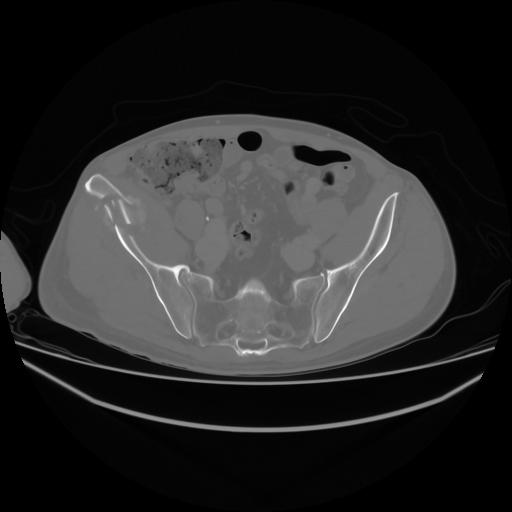

4 CUERPO,CE,Axial,3.0,CUERPO,,